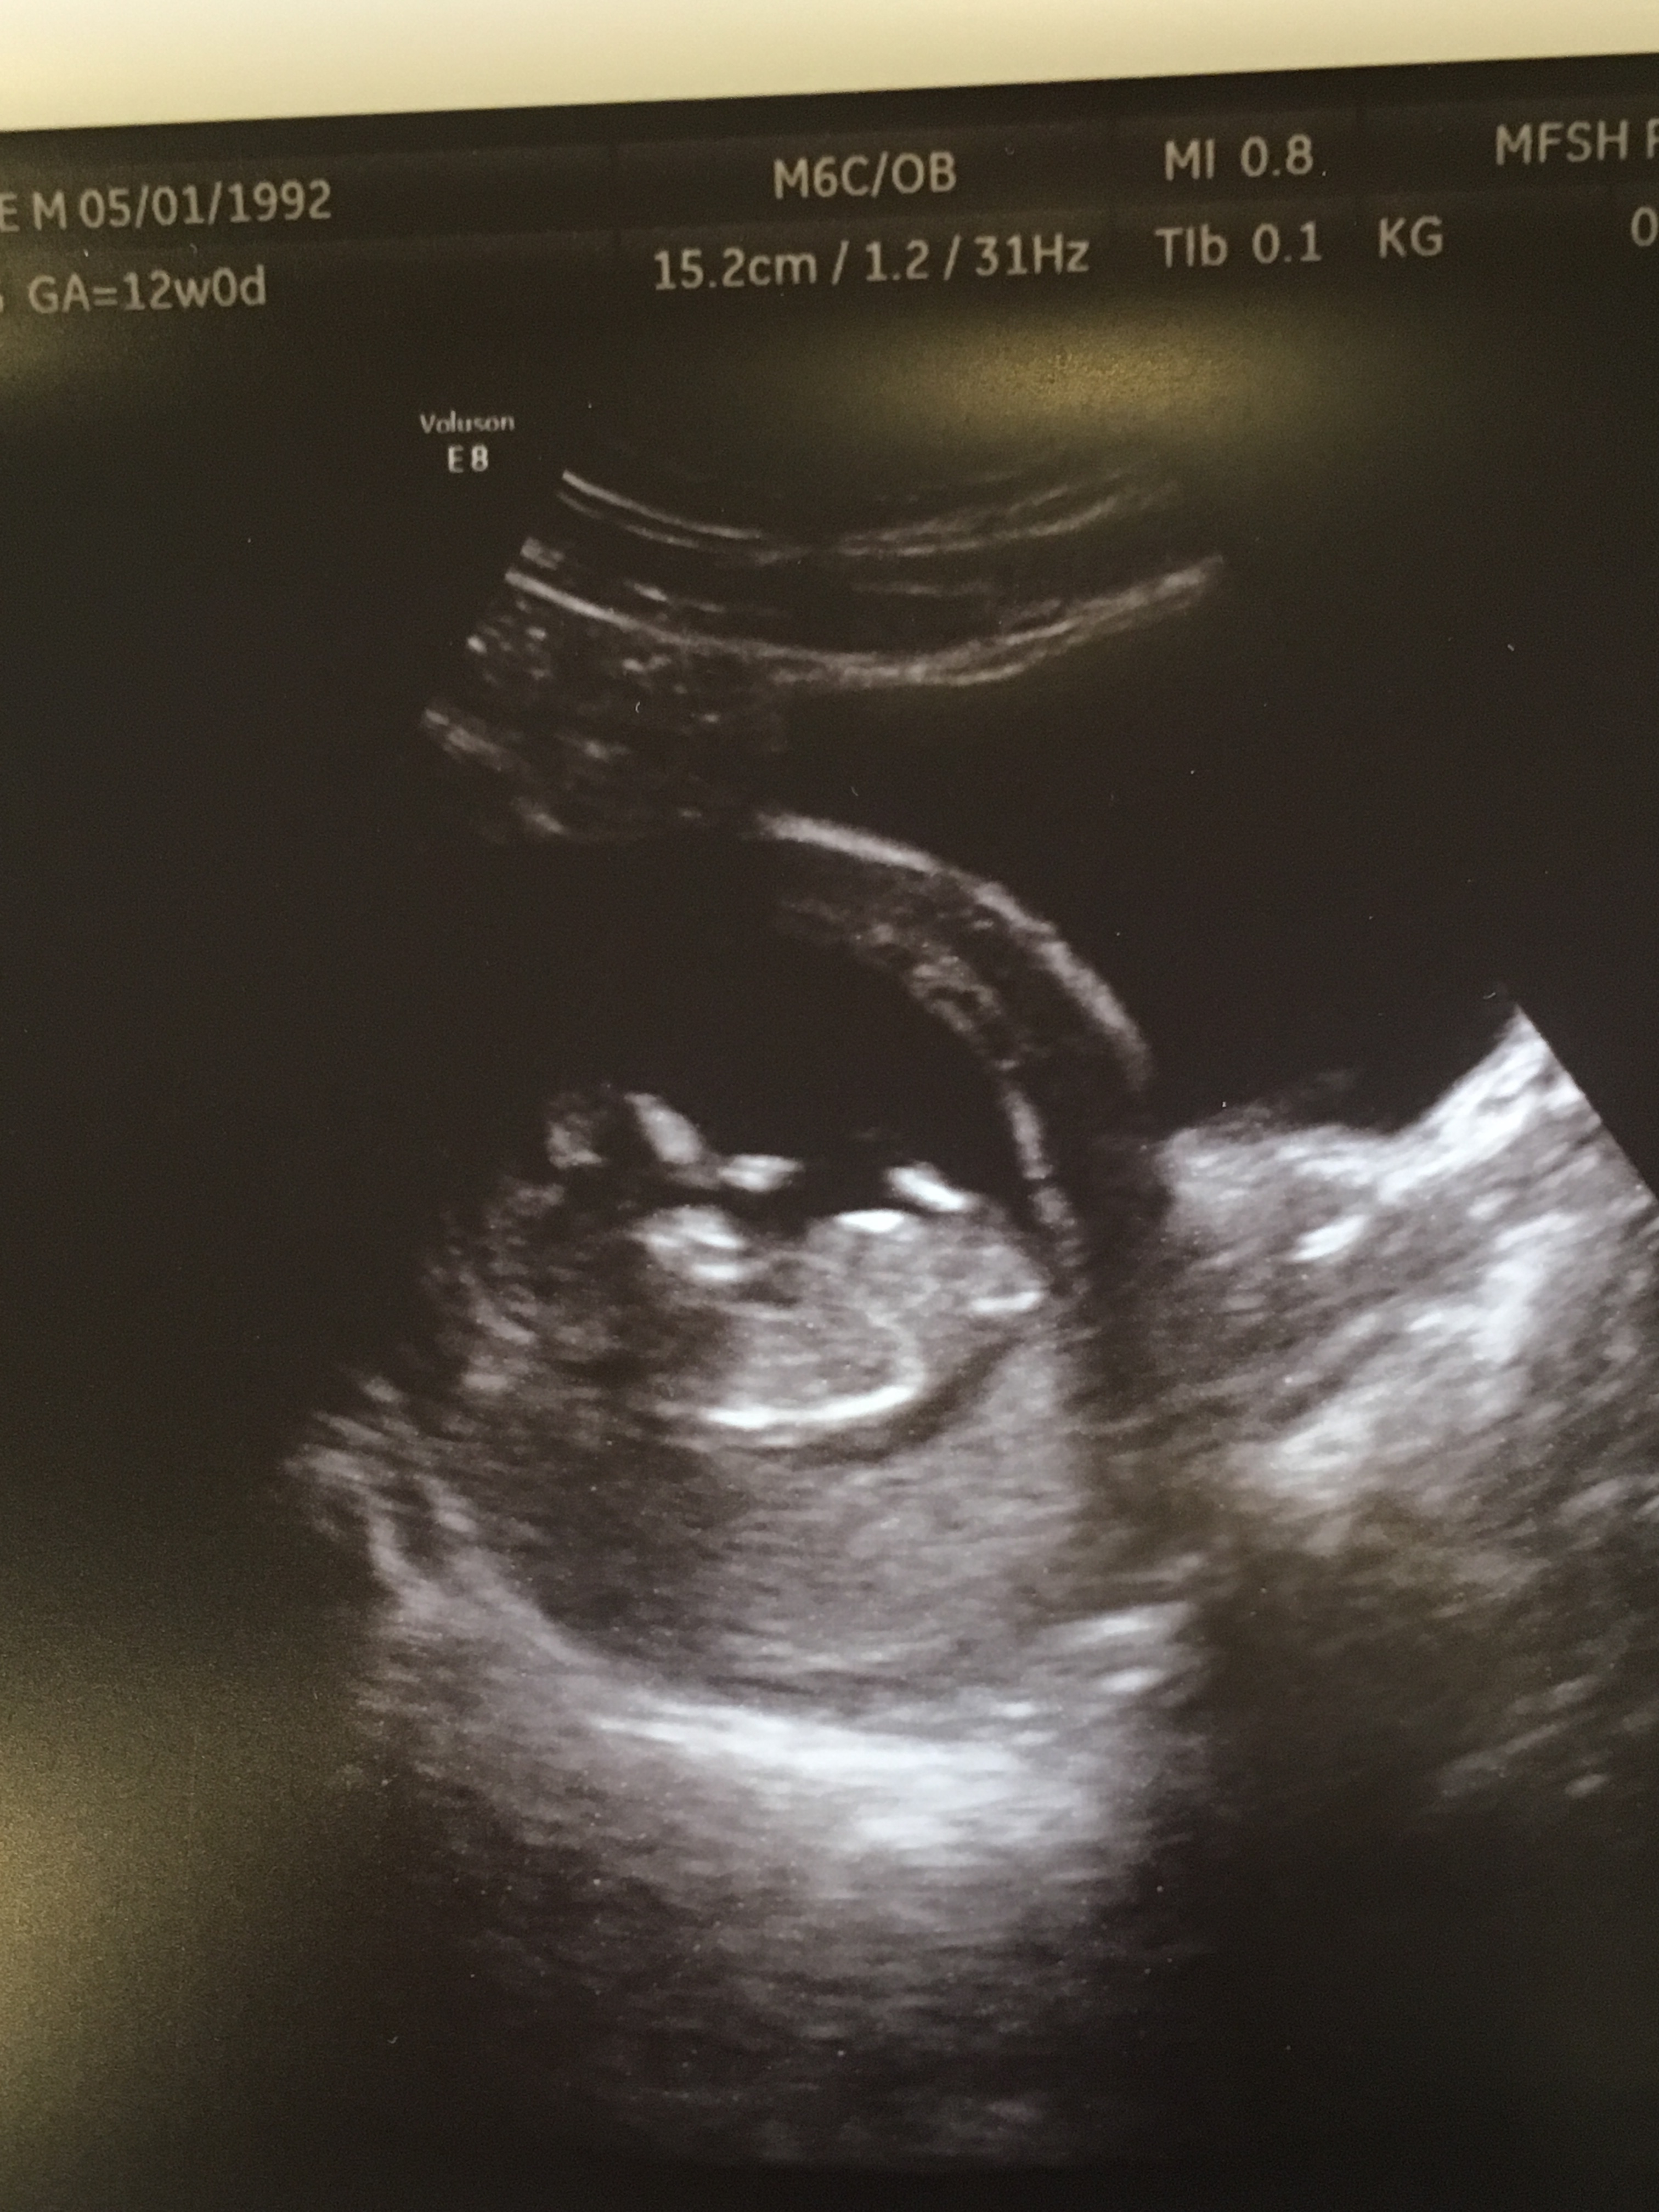

Attachment 36671

This one, but I think it's the cord, not the nub.

There is a slight hint of a nub there, but 12+0 is a bit too early for gender. When is your next scan?

Sorry, I am not seeing a good nub to guess.